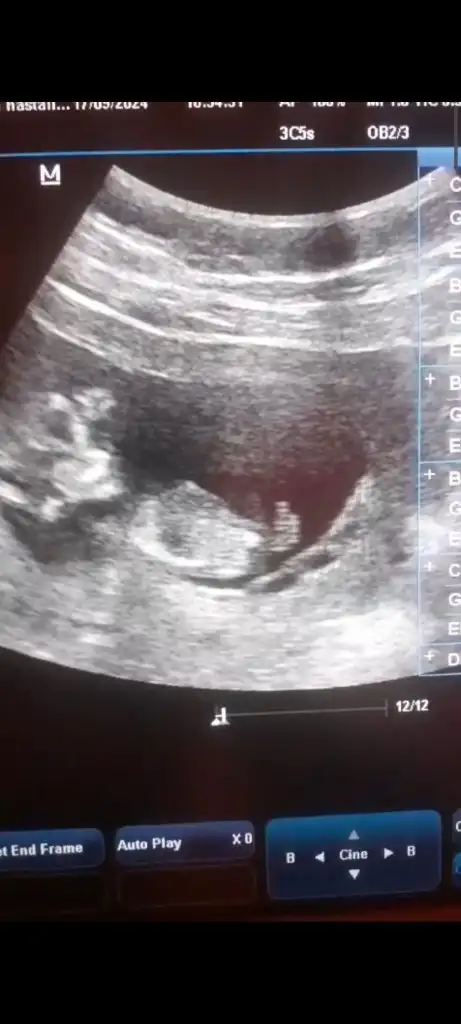

Kaç haftalıkCinsiyet tahmini yapabilirmisiniz bugun doktora gittim ama hic bisey söylemedi cok merak ediyorum simdiden teşekkürler Eki Görüntüle 3480222

Hiç anlamam da içimden kız gibi geçti hayırlısı olsun inşallahCinsiyet tahmini yapabilirmisiniz bugun doktora gittim ama hic bisey söylemedi cok merak ediyorum simdiden teşekkürler Eki Görüntüle 3480222